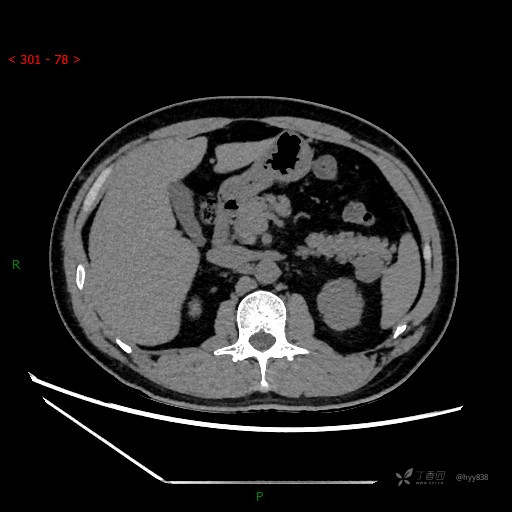

胰腺CT平扫

增强动脉期

增强静脉期

CT值

42hu 48hu 57hu